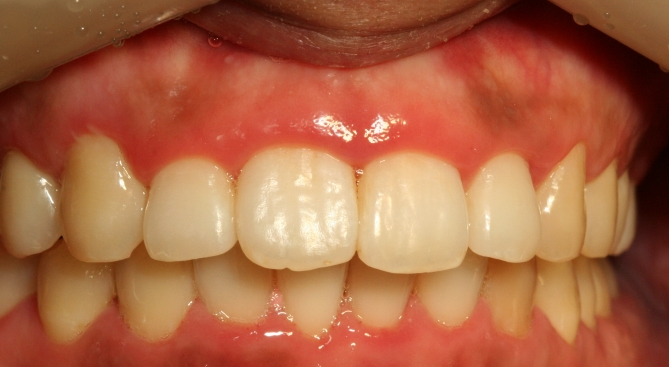

어떻게 변했는지 사진 보세요.

잘 되었지요?

발치하지 않고도 토끼이나 돌출된 앞니는 이렇게 변할 수 있습니다.

아까 위에서 봤던 틀어진 두 개의 앞니가

지금 보시면 가지런히 펴진 것이 보이시죠

빗발치로 이렇게 예쁘게 교정될 수가 있습니다.